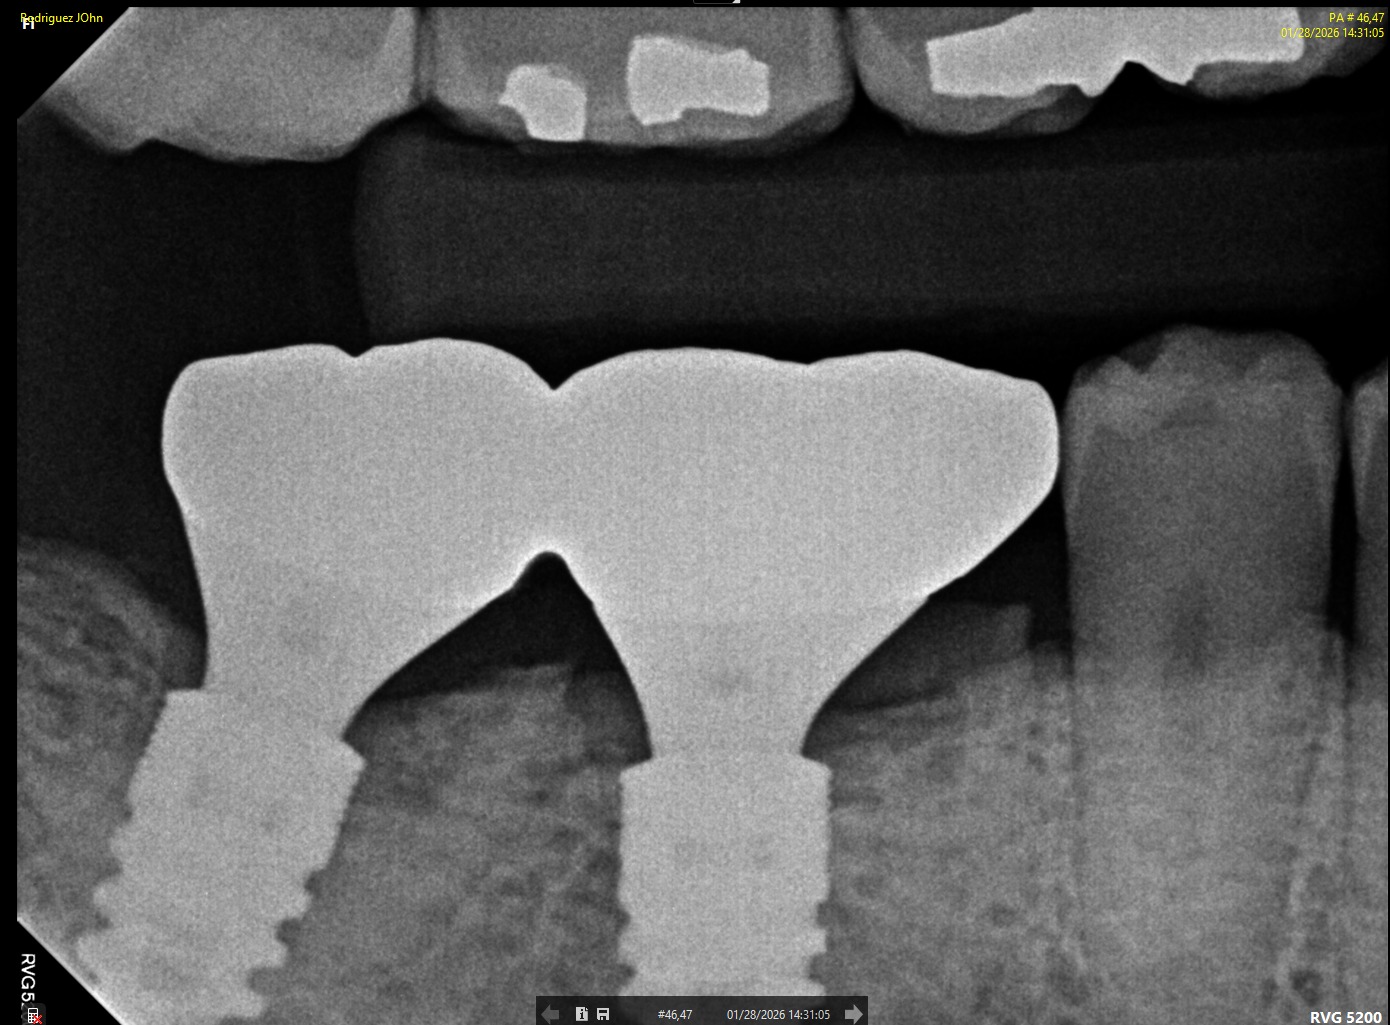

FOLLOW-UP - 2026

At the three-year follow-up:

• Peri-implant bone levels remained stable

• Soft tissues demonstrated healthy morphology and color

• The restorations maintained functional integrity under occlusal load

Both clinical and radiographic evaluations confirmed long-term hard and soft tissue stability, validating the treatment protocol and implant system used.